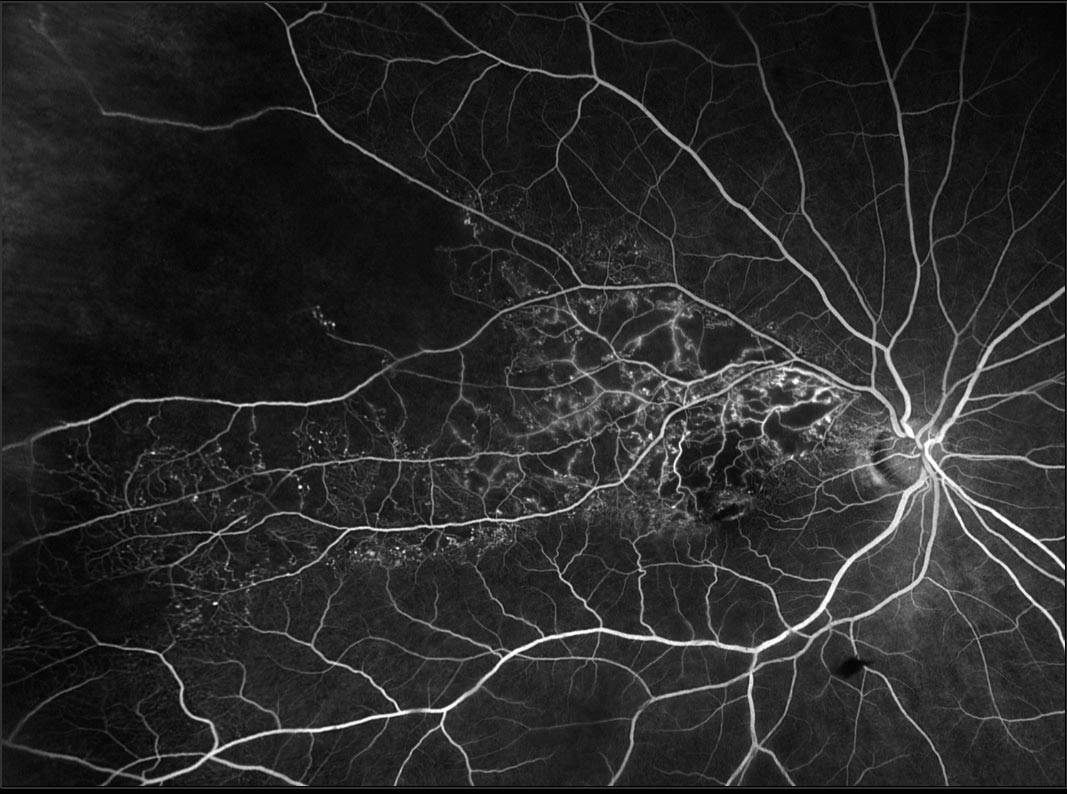

Fluorescein Angiography

A dye is injected into your vein, and pictures are taken as the dye flows through the retinal blood vessels. This test highlights areas where veins are blocked or leaking, and identifies regions of the retina that are not receiving enough oxygen (ischemia).